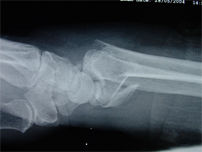

Smith's fractures

The Smith's fracture is a fracture sustained from a fall on a bent wrist. Instead of the broken bone being shortened, radially deviated and dorsally angulated as in a Colles fracture the Smith's fracture is shortened, ulnarly deviated (towards the little finger), and volarly deviated (towards the palm).

This is an unstable fracture and although can be treated with conservative means in a Smith's Plaster (a cast extending above the elbow with the wrist bent backwards), the fractures tend to displace and most people now operate on these.